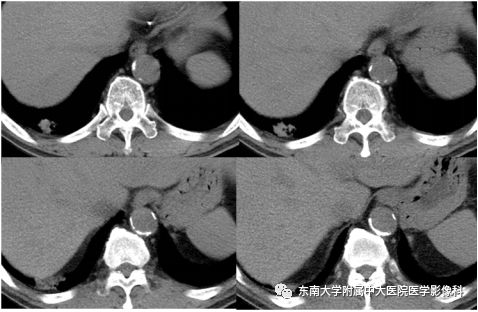

病史

男,66岁,因“咳嗽、咳痰7天”入院